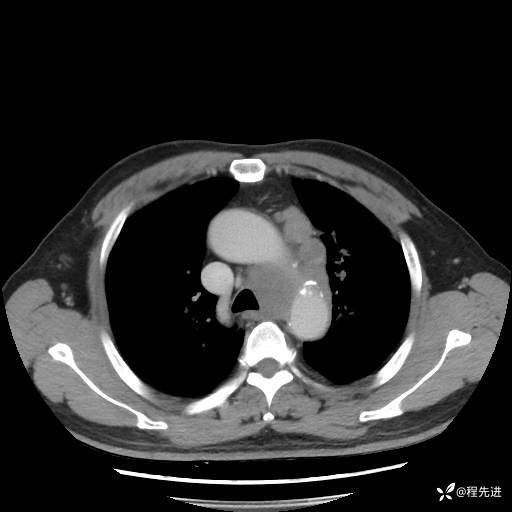

患者性别:男

患者年龄:57岁

简要病史:声嘶2月余

CT平扫+增强: